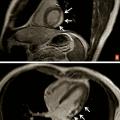

Il s’agit d’une péricardite aiguë virale bénigne à laquelle s’associe une atteinte myocardique. Elle représente environ 30 % des cas. Le diagnostic repose le plus souvent sur l’élévation concomitante de la troponine sur le bilan biologique. Selon les descriptions de la douleur et l’aspect ECG, le diagnostic différentiel avec un infarctus du myocarde peut être délicate. L’IRM cardiaque est alors l’examen clé pour éliminer formellement l’hypo­thèse de l’infarctus sur les séquences de rehaussement tardif. En cas d’infarctus, il y a un hypersignal sous-endocardique systématisé. En cas de myopéricardite, l’hypersignal est intramyocardique ou sous-épicardique, nodulaire et non systématisé, parfois associé à un décollement péricardique (fig. 2) ; l’anomalie n’est toutefois présente que dans 30 % des cas, et l’IRM normale n’élimine donc pas le diagnostic de myopéricardite. Si la douleur est au premier plan, la prise en charge est identique à celle de la péricardite ; en absence de douleur, le traitement est débattu et non systématique.

IRM cardiaque

Inutile en cas de péricardite aiguë virale bénigne, elle peut s’avérer utile en cas d’élévation concomitante de la troponine ou en cas de doute sur un syndrome coronaire aigu sans anomalie notable sur la coronarographie. Dans ces conditions, l’IRM est l’examen le plus sensible pour éliminer un infarctus sous-endocardique. Dans le cas d’une myopéricardite, les séquences de rehaussement tardif peuvent révéler des hypersignaux intramyocardiques ou sous-épicardiques (v. Formes cliniques).